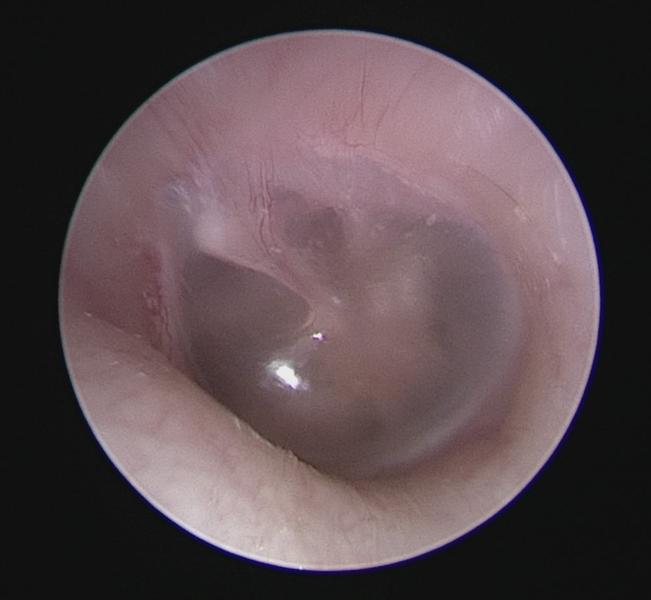

Normal Tympanic Membrane